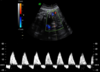

diastole reversa na arteria umbilical

diastole zero na arteria umbilical

Ducto venoso onda A reversa